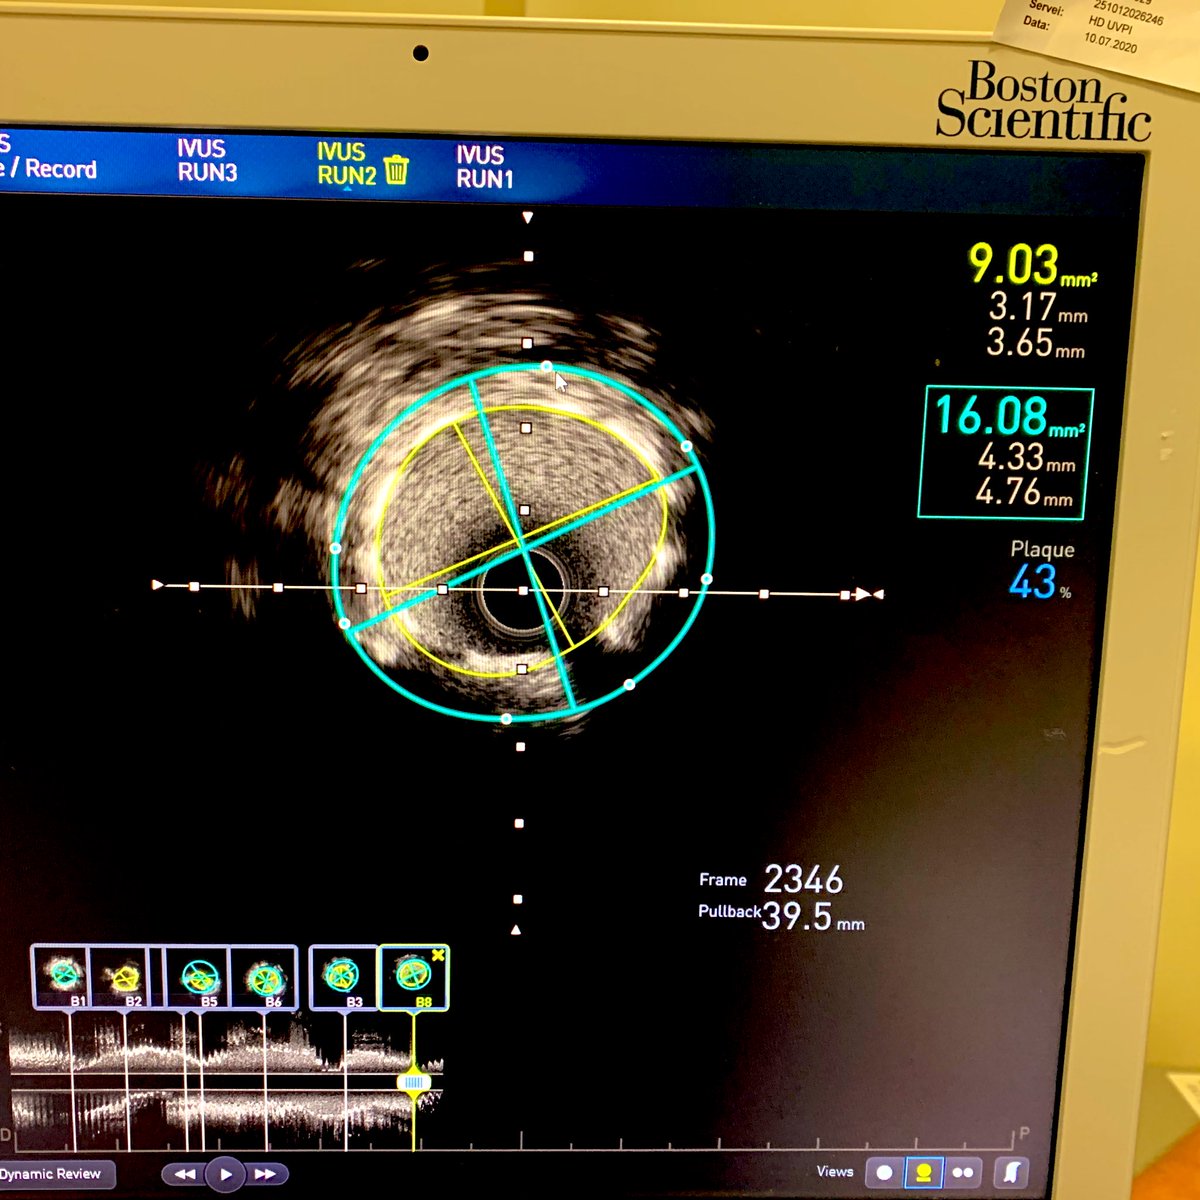

53 años , angina de esfuerzo, angiotac de coronarias con estenosis no significativa, angiograficamente la lesión del TCd del 50%. La importancia de guiar la PCI con imagen. cutting y SYNERGY MEGATRON @BSCCardiology @dragustinr @M_AbrL @drgianma